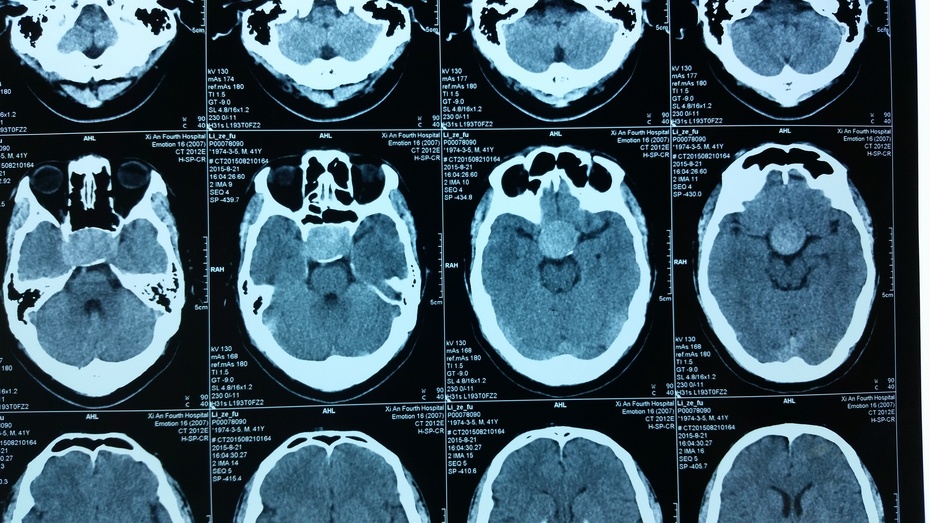

鞍区病变的ctmri诊断

蝶鞍区ct:右侧鞍旁见软组织密度影,包绕右侧海绵窦,右侧视神经管